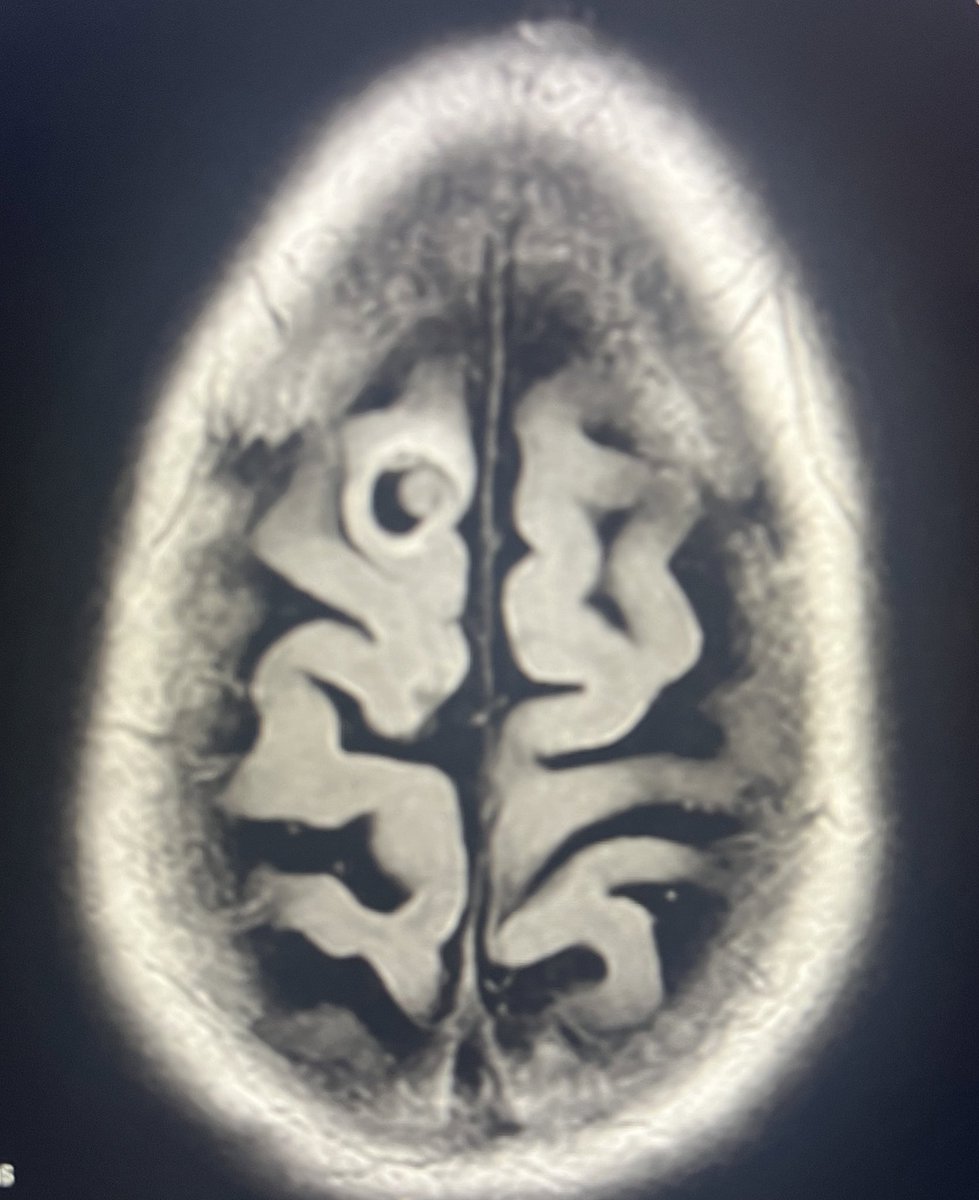

Measles is a highly contagious virus with a primary case reproduction number of 12 to 18.

It is currently spreading rapidly owing to reduced measles vaccination coverage